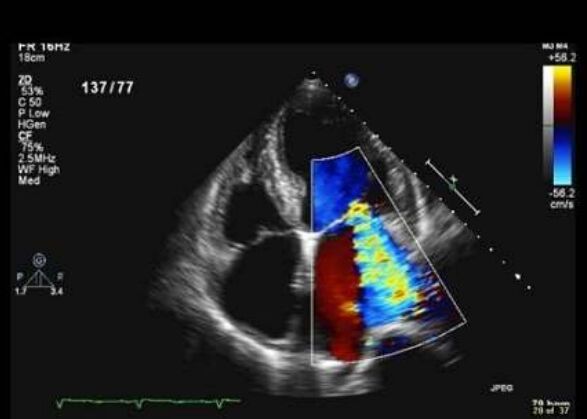

33.如圖所示,依此心臟超音波可以得到的資訊 依此心臟超音波可以得到的資訊,下列何者錯誤? (A)左心房擴大 (B)有主動脈瓣狹窄 (C)有明顯二尖瓣膜逆流 (D)沒有心包膜積水